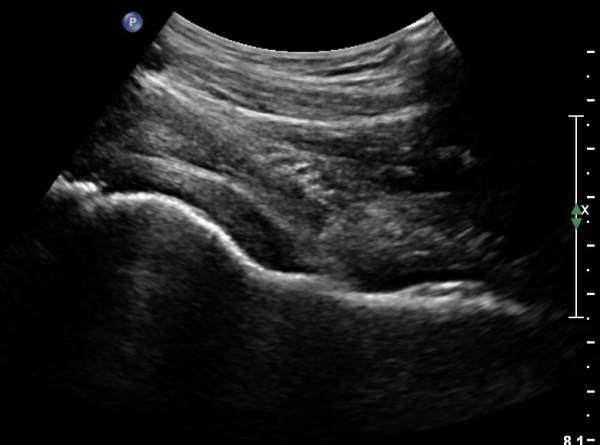

[¾ûµ¢ÀÌ] °í°üÀý Ãæµ¹ÁõÈıº¿¡ÀÇÇÑ È°¾×¸·¿° ÁÖ»çÄ¡·á